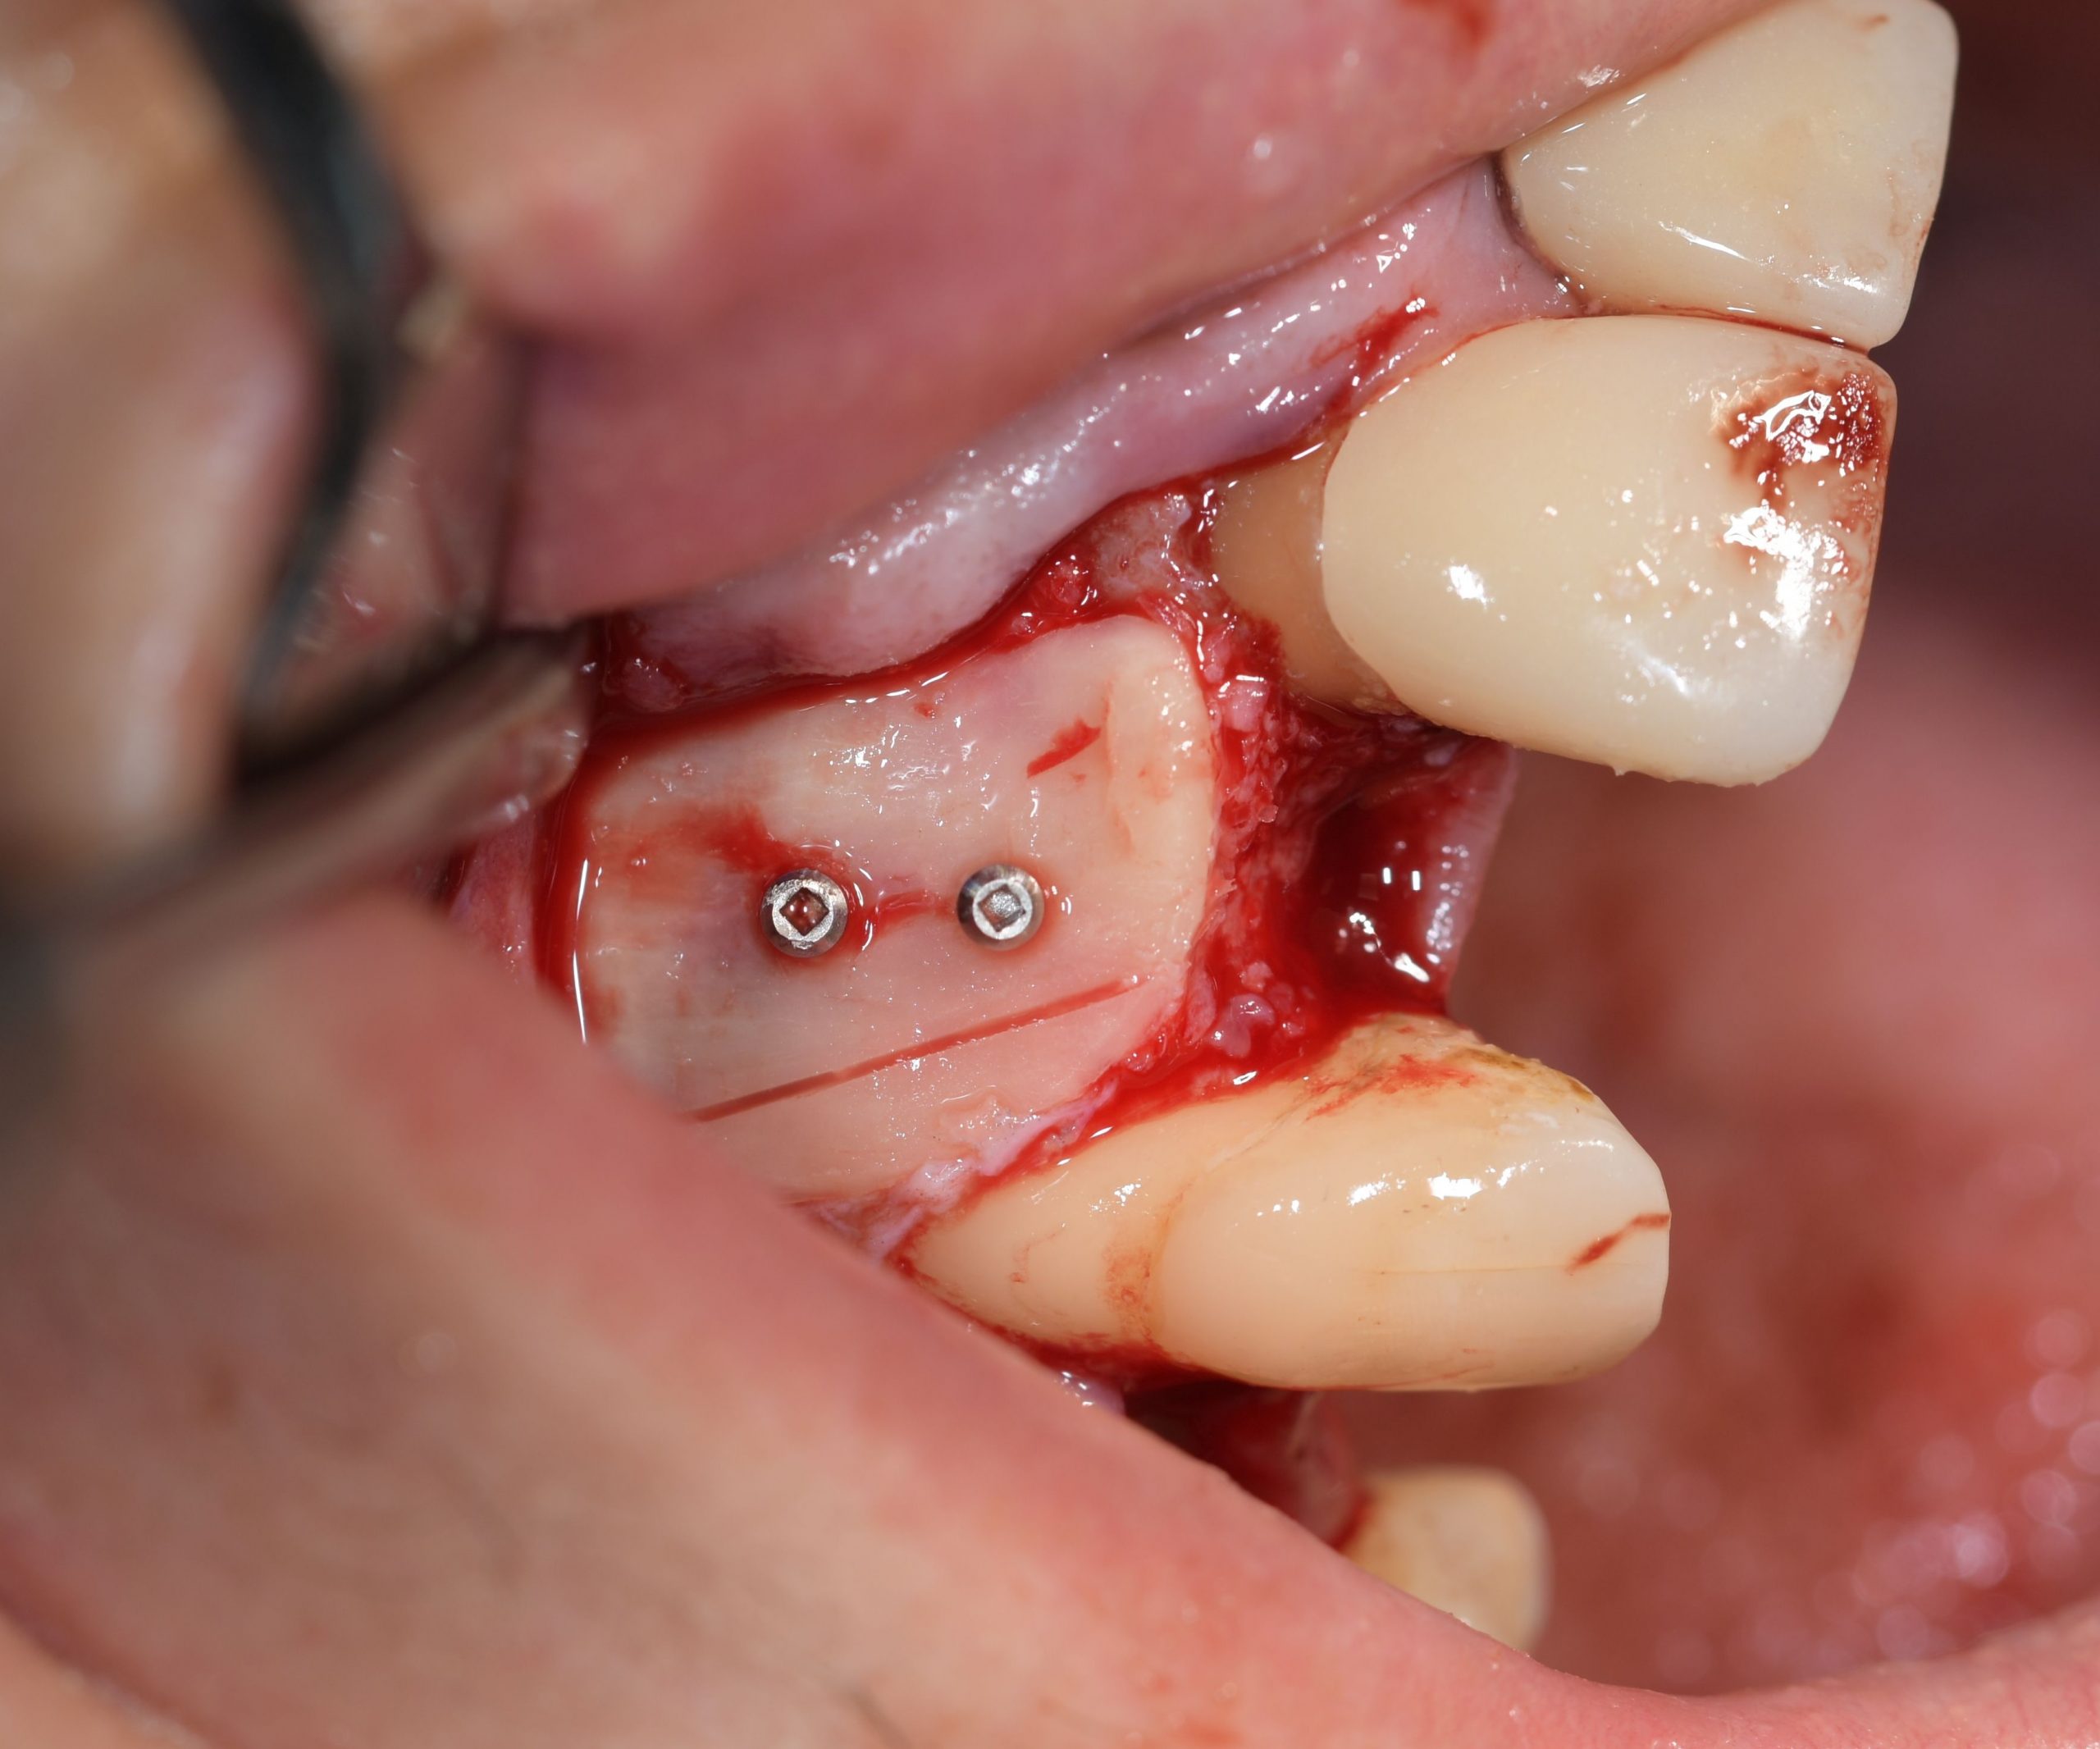

Each case is documented with clinical pictures before, after and during operation. For most of the cases there is surgical video. CBCT before, in the OP day and 4 months after, or longer period of time will demonstrate the volume of buccal bone and soft tissue. Depends of time available, between 13 and 20 clinical cases can be shown.

2. Compromised socket case

- Creation of buccal wall defect

- Implant installation and bone defect evaluation

- Bone harvesting with calibrated concave chisel

- Shaping and adapting the cortico-cancellous graft

- Grafting and socket sealing with custom-made provisional abutment